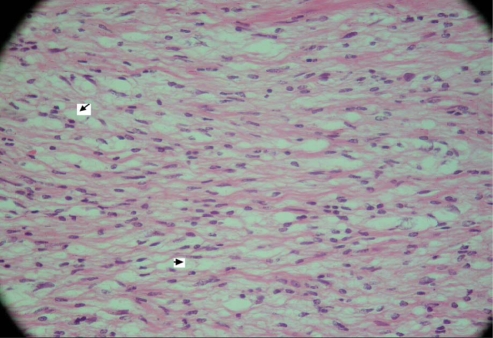

Fig. 5.

This tumour is mainly composed of loose Antoni B tissue. There are small foci of increased cellularity but no definite nuclear palisading is noted. Elsewhere, the tumour contains hyalinised thick-walled blood vessels. Mitotic figures are not seen. The appearances are consistent with a conventional schwannoma (WHO grade I) (case 2)